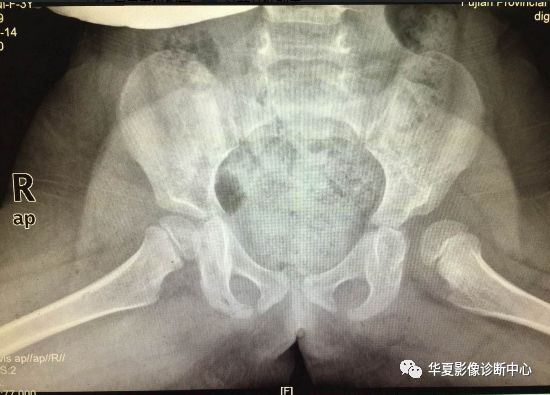

上图:骨盆蛙式位

6. Shenton线:

正常闭孔上缘弧形线与股骨颈内侧弧形线相连在一个抛物线上,称为Shenton线,髋脱位、半脱位病例,此线完整性消失。

7.外侧线(Calve线)

外侧线(Calve线)即髂翼的外侧面与股骨颈外侧面的弧形连线,正常为连续的。